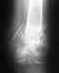

Без снимков определенное что-то не сказать ни про повреждение, ни про соответствие ему лечения. Так, абстрактно, можно только упомянуть, что отек при переломе может быть в течение нескольких месяцев.